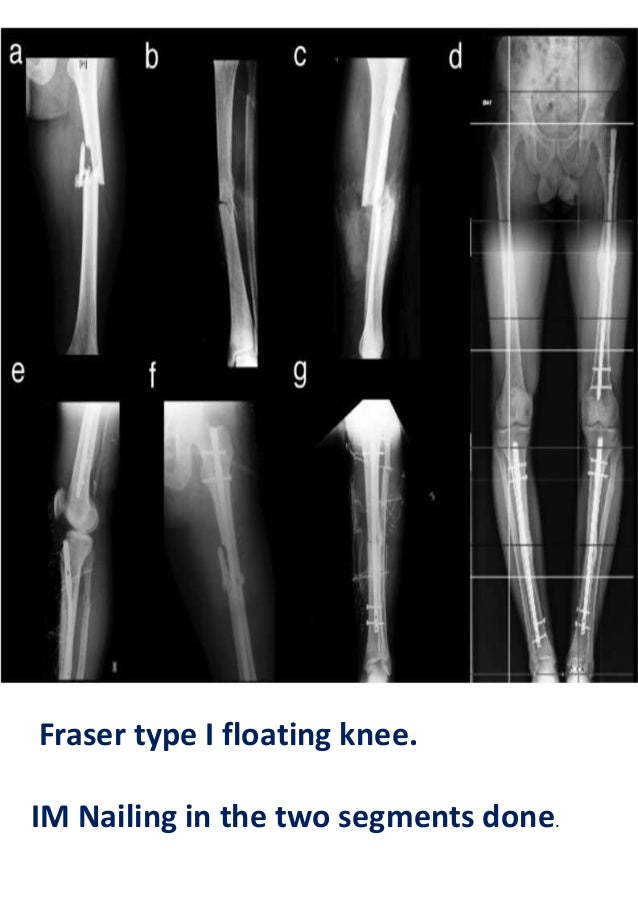

From www.slideshare.net

From www.slideserve.com